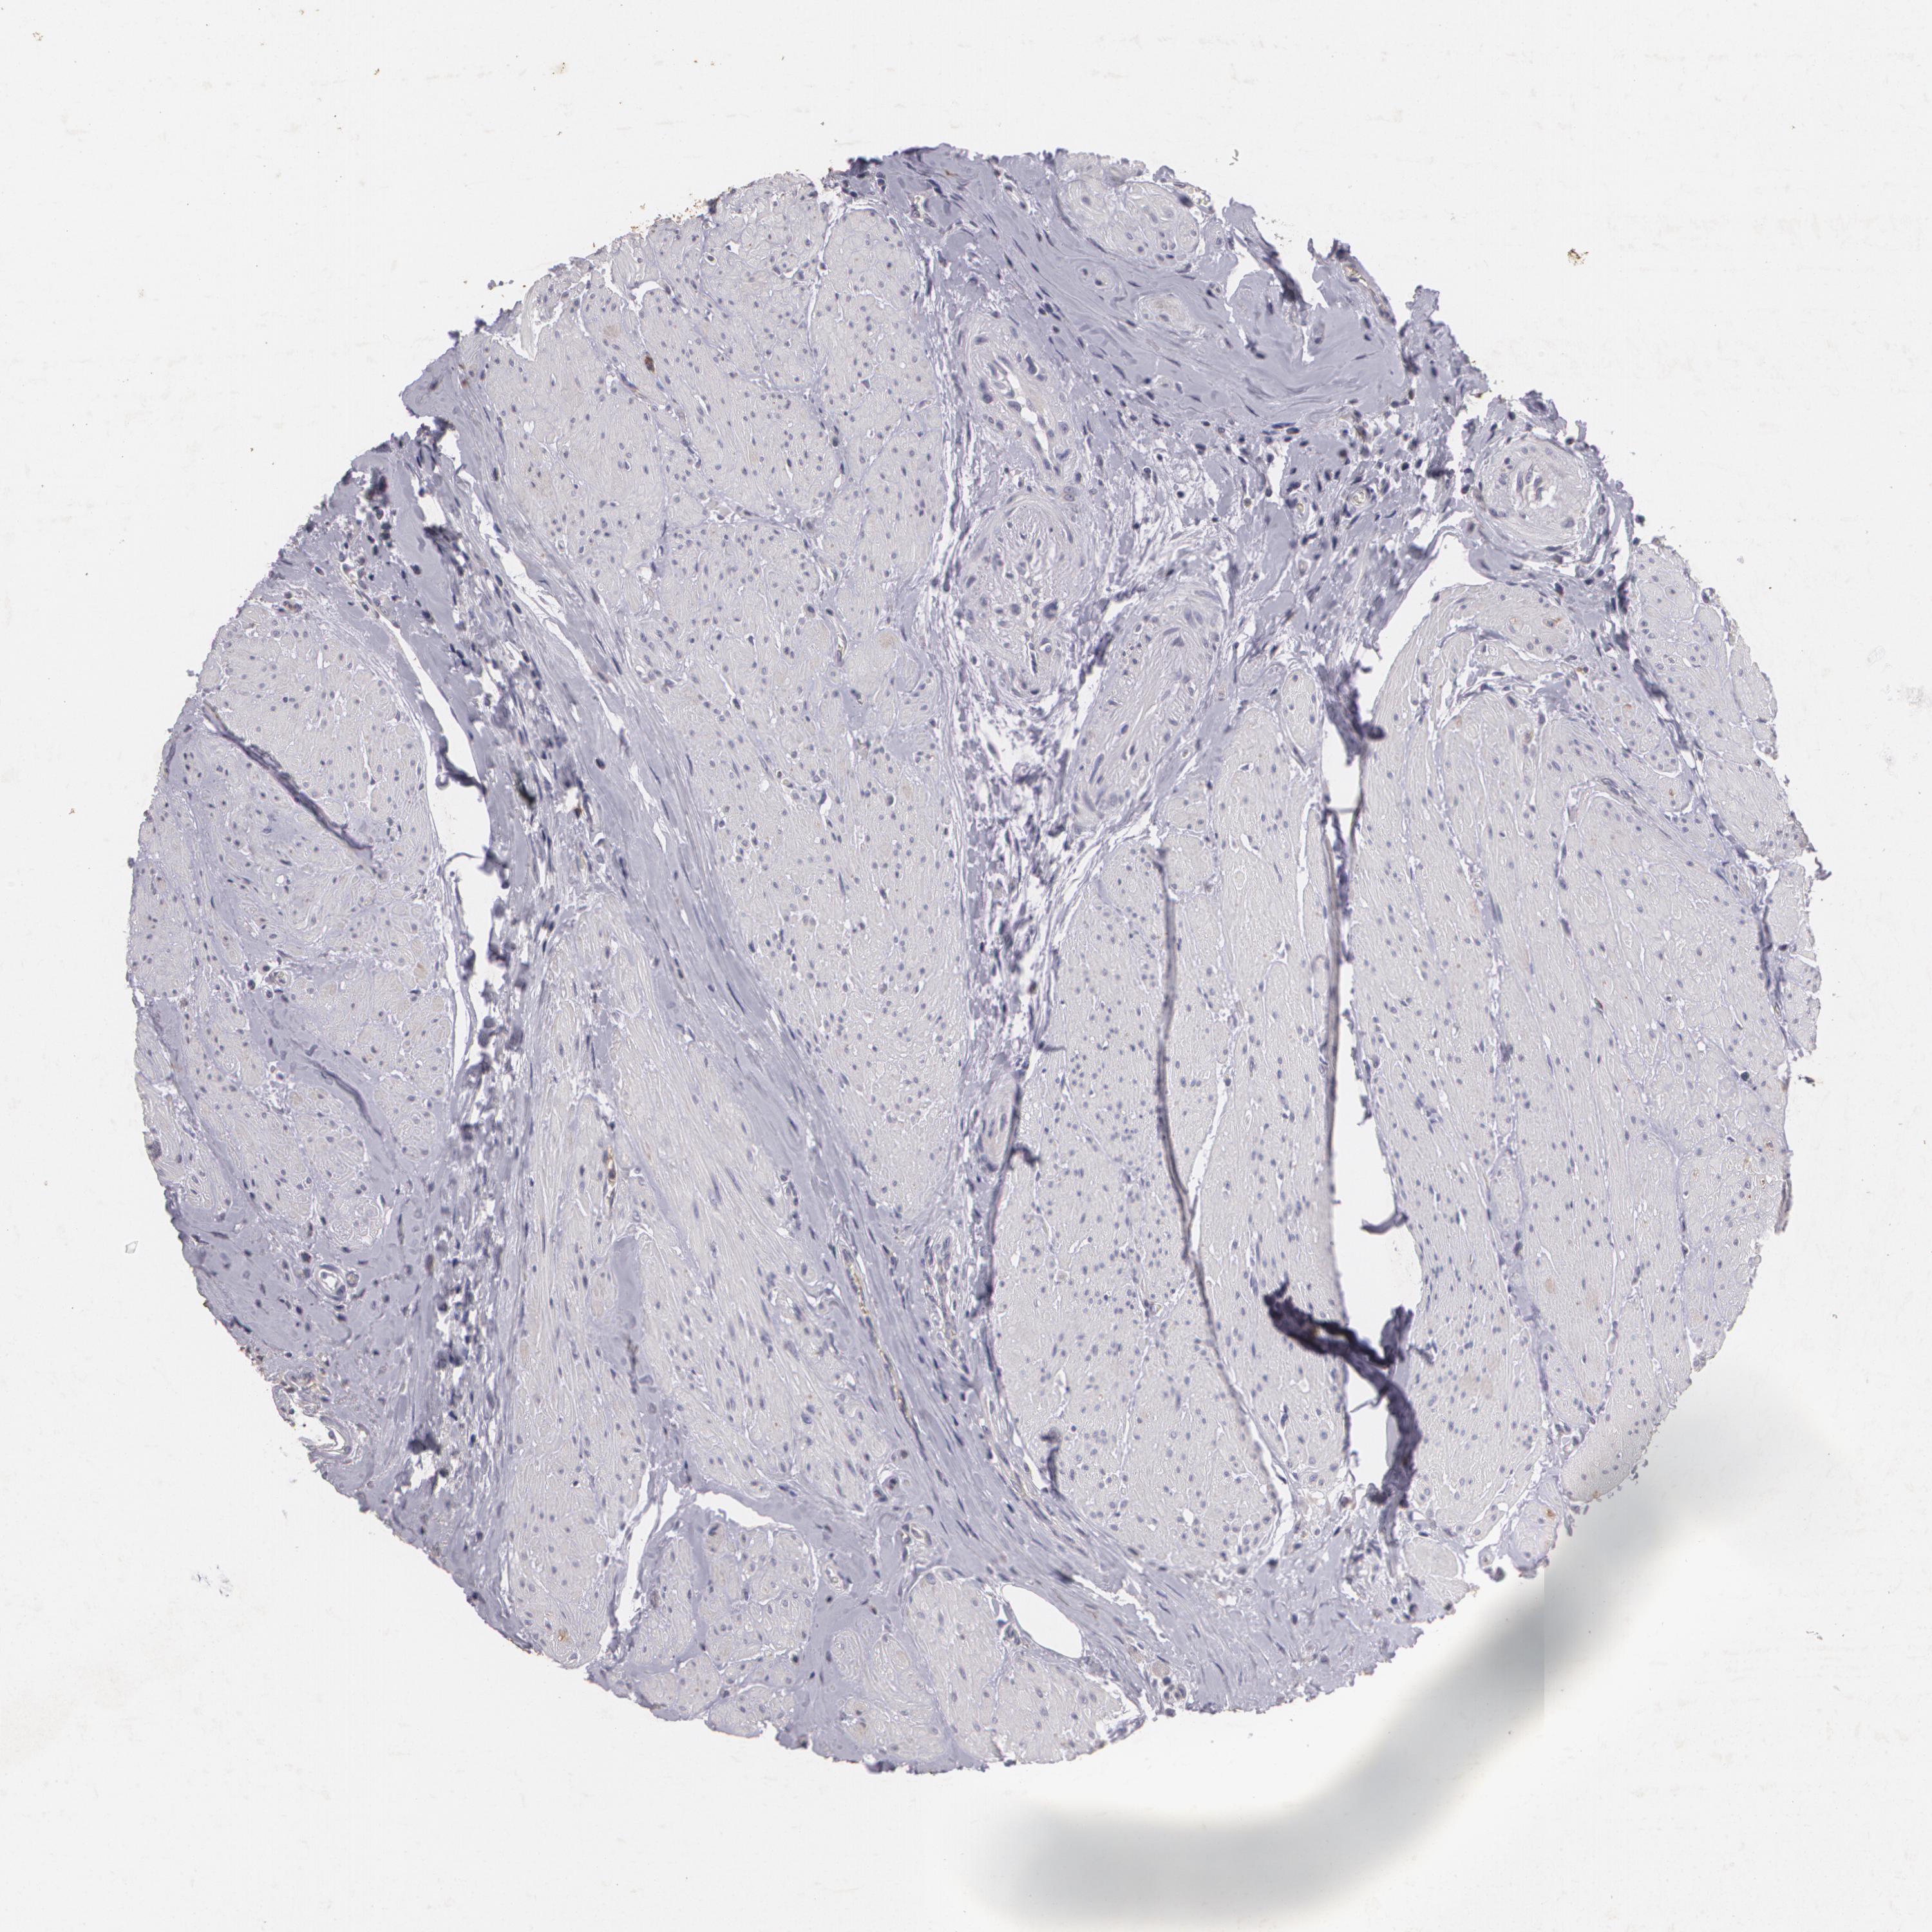

UROTHELIAL CANCER - Protein expressioni

A mouse-over function shows sample information and annotation data. Click on an image to view it in a full screen mode. Samples can be filtered based on level of antibody staining by selecting one or several of the following categories: high, medium, low and not detected. The assay and annotation is described here.

Note that samples used for immunohistochemistry by the Human Protein Atlas do not correspond to samples in the TCGA dataset.

Antibody stainingi

Antibody staining in the annotated cell types in the current human tissue is reported as not detected, low, medium, or high, based on conventional immunohistochemistry profiling in selected tissues. This score is based on the combination of the staining intensity and fraction of stained cells.

Each image is clickable and will lead to virtual microscopy that enables deeper exploration of all samples and also displays staining intensity scores, fraction scores and subcellular localization as well as patient and tissue information for each sample.

Antibody HPA016422

Antibody CAB001977

Staining

High

Medium

Low

Not detected

Intensity

Strong

Moderate

Weak

Negative

Quantity

>75%

75%-25%

<25%

None

Location

Nuclear

Cytoplasmic/membranous

Cytoplasmic/membranous,nuclear

Urothelial carcinoma, Low grade

Urothelial carcinoma, High grade

Adenocarcinoma, NOS